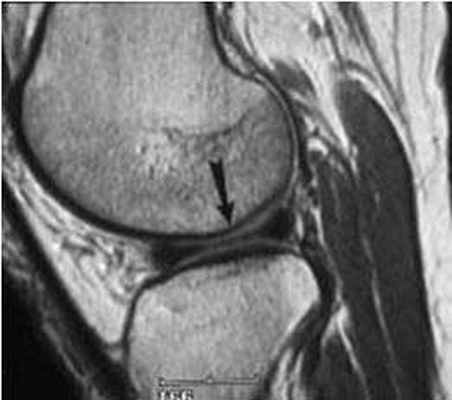

МРТ коленного сустава. Т2-взвешенная сагиттальная МРТ с подавлением сигнала от жира. Разрыв медиального мениска

С помощью МРТ удается точно определить наличие и полноту разрыва крестообразных связок(свыше 90%) и хорошей в плане выявления разрывов менисков (80-85%).

Методика МРТ может выявить самые ранние изменения различных структур сустава. Например, она незаменима при оценке состояния менисков. Степени их изменения на МРТ:

- 0 степень – нормальное состояние мениска;

- I степень – в теле мениска есть очаговый сигнал усиленной интенсивности, который еще не доходит до края мениска;

- II степень – появление в мениске линейного сигнала усиленной интенсивности, не доходящего до его краев;

- III степень – сигнал усиленной интенсивности достигает крайней части мениска.

О разрыве мениска говорят только изменения III степени.

Для диагностики важна еще и форма мениска. В норме он в определенной плоскости имеет форму бабочки. Любые отклонения могут указывать на возможный разрыв.